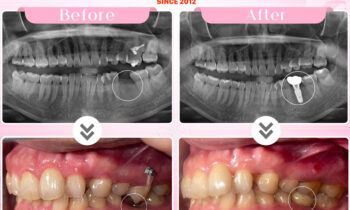

Ca kết hợp giữa chỉnh nha và cấy implant tạo nên tổng thể hài hoà

Một ca kết hợp giữa chỉnh nha và cấy ghép implant tạo nên một tổng thể hài hoà cho nụ cười của bạn Q tại Nha khoa Thiện An???? Sau khi niềng răng, nhờ sự hỗ trợ của các khí cụ chuyên dụng, hàm răng sẽ được nắn chỉnh về đúng vị trí trên cung…